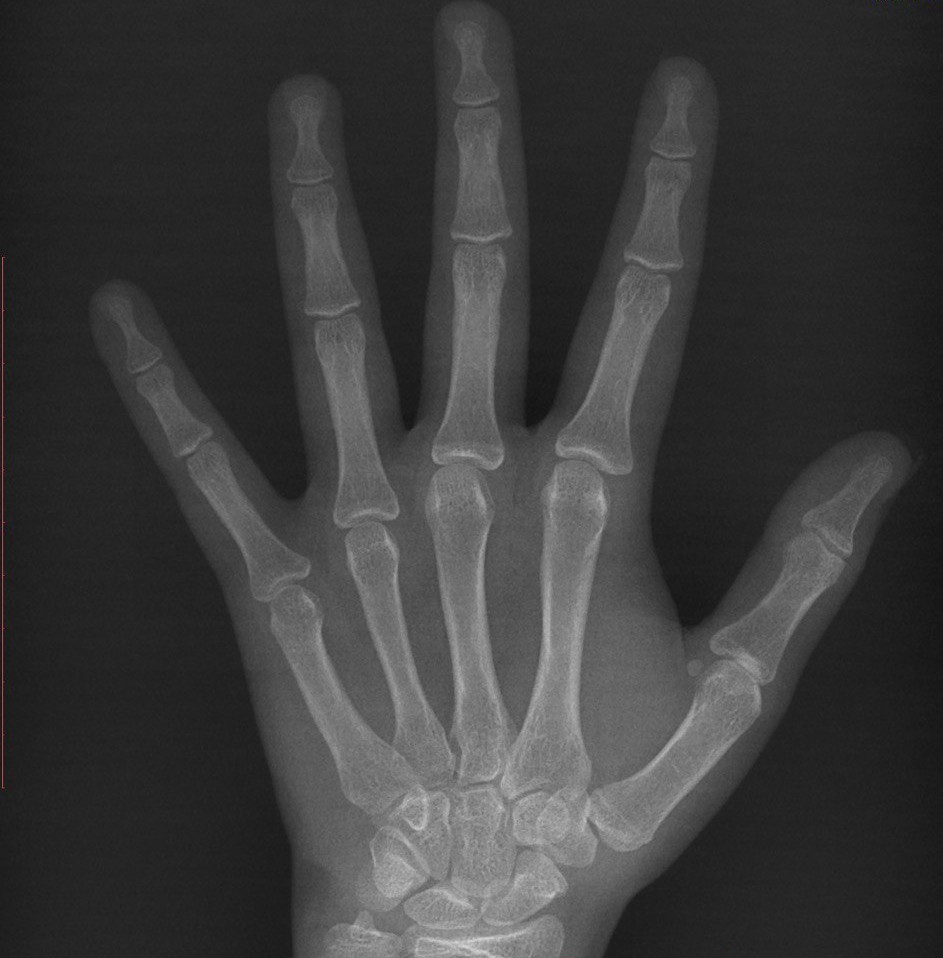

Зоны роста.РостЗдравствуйте, мне не давно исполнилось 18 лет, пару недель назад, сегодня я решил проверить свои зоны роста, рентгенолог сказал, что зоны роста закрыты, Я на это и рассчитывал, так как у меня был ранний пубертат, мой рост составляет 181-182 утром, 178-179 вечером, рост отца-173, рост матери 165, рост деда 167, рост бабушки 163, также у бабушки есть родной брат рост которого составляет 187-190см.Так же мой вес составляет 90-93кг (преимущественно мышечная масса).Я бы хотел спросить возможен ли дальнейший рост, хоть на 1-2см, при том что мои зоны роста на кистях закрыты, именно рост, а не вытягивание с помощью турника или плавания, какой у меня примерно костный возраст, если это можно определить по снимку, какой мой генетически потенциал и смог ли я его реализовать, ведь я жил в очень хороших условиях и единственные факторы которые могли оказать влияние на мой рост это ранний пубертат, небольшой недостаток сна (6-7 часов) и силовые тренировки с 15 лет. |

Здравствуйте. Зоны роста закрыты. Свой потенциал вы реализовали. В 15 лет зоны роста были закрыты не полностью. |